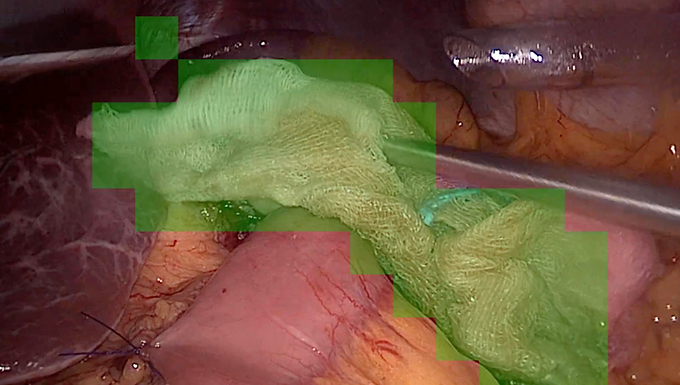

Surgical gauze is routinely used during operative procedures for blood absorption, tissue manipulation, and maintaining a clear surgical field. Failure to detect or account for gauze intra-operatively can lead to serious complications, including retained surgical items and postoperative infections.

Surgical video-based gauze detection presents several challenges:

Gauze appearance varies widely (dry vs blood-soaked, folded, crumpled)

Color and texture can change rapidly due to bleeding

Partial occlusion by instruments and tissue

Deformation and motion during manipulation

Visual similarity to surrounding tissue or fat when saturated

These factors make reliable gauze detection difficult, especially under real-world surgical conditions. The problem is to design a vision-based system that can robustly detect and track surgical gauze across frames or video sequences with high reliability.